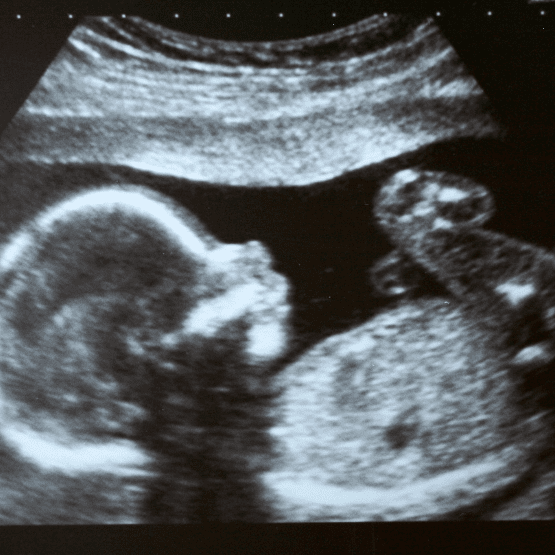

Doğum öncesi işitme kaybı, bebeğin anne karnındayken veya doğum anında meydana gelen bir dizi faktörden kaynaklanan duymama sorunudur. Bu durum, genetik bozukluklar, annenin hamilelik sırasında geçirdiği enfeksiyonlar veya kullanılan bazı ilaçlar gibi farklı nedenlere bağlı olabilir. Konjenital işitme kaybı olarak da bilinen bu durum, işitme kaybının en yaygın türlerinden biridir ve hem tek kulakta hem de her iki kulakta birden görülebilir.